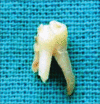

Dental anomalies of number and forms may occur in the primary and permanent dentition. Various terms have been used to describe dental twinning anomalies: Germination, fusion, concrescence, double teeth, conjoined teeth, twinned teeth, geminifusion, and vicinifusion. Fused tooth is a developmental anomaly that is seen more frequently in the primary than the permanent dentition. Double tooth involving deciduous anterior teeth is found mostly in the mandible. Very few cases of nonsyndromic double primary molar have been reported in the literature. The succeeding permanent tooth is often found missing congenitally in the same region. This article reports a very rare unilateral occurrence of an anomalous, primary mandibular first macromolar formed by fusion with a dysmorphic premolar like supernumerary tooth in deciduous dentition period. Instead of agenesis of succedaneous tooth, the double tooth has been succeeded by normally developing mandibular first premolar in the same region.